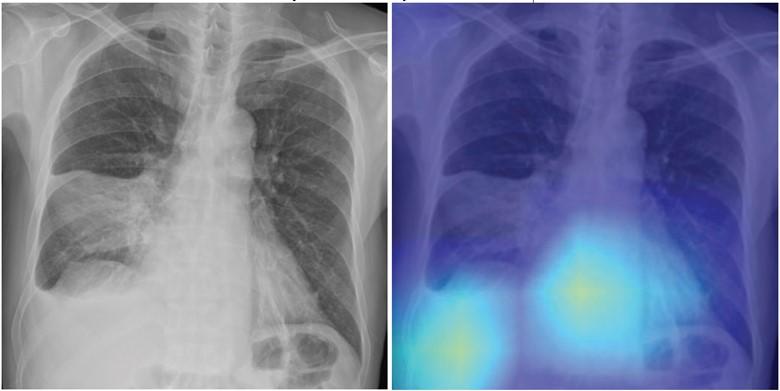

69-year-old male patient with CAP. Left: Chest radiograph shows area of consolidation involving right lower lung consistent with pneumonia, as well as right pleural effusion. DL model predicted risk of 30-day mortality of 9%. Right: Gradient- weighted class activation map shows that model prediction was influenced by separate area of image corresponding with heart and liver (yellow and light blue colors). Patient’s CURB-65 score was 4. Patient recovered from pneumonia and remained alive at time of present investigation (14 months after pneumonia diagnosis).

June 16, 2023 — According to an accepted manuscript published in ARRS’ own American Journal of Roentgenology (AJR), a deep learning-based model using initial chest radiographs predicted 30-day mortality in patients with community-acquired pneumonia (CAP), improving upon the performance of an established risk prediction tool (i.e., CURB-65 score).

“The deep learning (DL) model may guide clinical decision-making in the management of patients with CAP by identifying high-risk patients who warrant hospitalization and intensive treatment,” concluded first author Eui Jin Hwang, MD, PhD, from the department of radiology at Seoul National University College of Medicine in Korea.

Ultimately, a DL model using initial chest radiographs predicted 30-day all-cause mortality in patients with CAP with AUC ranging from 0.77 to 0.80 in test cohorts from different institutions. Additionally, the model showed higher specificity (range, 61–69%) than the CURB-65 score (44–58%) at the same sensitivity (all p < .001).